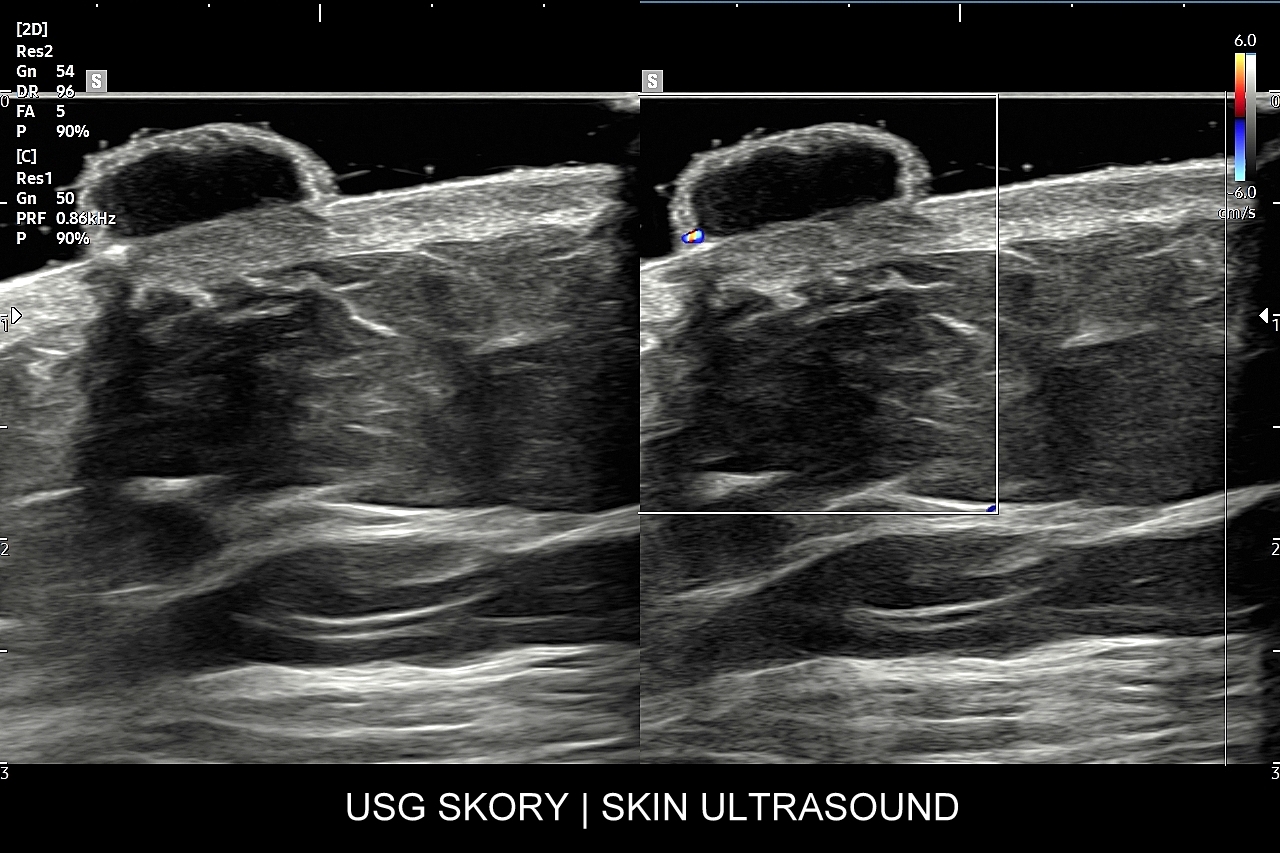

Badanie USG skóry i powłok jest metodą diagnostyczną, która swoją czułością oraz dokładnością przewyższa w ocenie patologii powłok badanie rezonansem magnetycznym. W obrębie powłok ciała w badaniu USG najczęściej rozpoznaje się różnorodne guzy oraz stany zapalne. Wśród guzów dominują łagodne tłuszczaki, kaszaki i torbiele inkluzyjne, a także przepukliny. U młodszych pacjentów często wykrywa się naczyniaki. Rzadziej spotkane są guzy złośliwe jak mięsaki, czy przerzuty nowotworowe. W pracowni USG dr Szczepańskiego poza wizualną oceną guzów powłok przeprowadzana jest ich ocena biologii w kontekście cech złośliwości i oceny przewidywalnego tempa wzrostu.

Badanie USG twarzy, często nie do końca fortunnie zwane USG skóry twarzy, to stosunkowo nowa metoda diagnostyczna wprowadzona we Wrocławiu do użytku przez dr Tomasza Szczepańskiego, a wykonywana w przypadku schorzeń z zakresu medycyny estetycznej, dermatologii, laryngologii, stomatologii i chirurgii. Wśród rozpoznań w badaniu USG skóry twarzy dominują choroby infekcyjne takie jak rozprzestrzeniające się w tkankach miękkich zapalenia i ropowice pochodzące od zapaleń zębów czy migdałków, powikłania ropne w przebiegu trądziku pospolitego lub różowatego, po iniekcjach wypełniaczy i po innych zabiegach z zakresu medycyny estetycznej. Kolejną dużą grupą patologii skóry twarzy są torbiele inkluzyjne, których przykładem są kaszaki, oraz guzy twarzy, wśród których dominują ziarniniaki jako odległe acz częste powikłanie depozycji wypełniaczy z kwasu hialuronowego.

USG twarzy wykorzystywane jest także do diagnozowania urazów twarzoczaszki, zarówno w obrębie tkanek miękkich (np. uraz zmiażdżeniowy tkanki podskórnej), jak i kości (np. złamanie kości jarzmowej, kości nosa); do oceny zaawansowania bruksizmu; oceny i kategoryzowania naczyniaków twarzoczaszki; diagnozowania zapaleń tętnic skroniowych; czy powikłań naczyniowych w medycynie estetycznej. Badanie USG twarzy służy również do oceny defektów kosmetycznych zarówno przed ewentualnymi zabiegami estetycznymi i plastycznymi, jak i po nich.